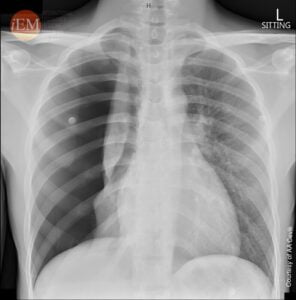

Диагнозата на пневмоторакс обикновено включва комбинация от физически преглед, медицинска анамнеза и образни изследвания, като рентгенография на гръдния кош, компютърна томография или ултразвук.

Иван незабавно е прегледан от екипа в спешното отделение и е назначена рентгенова снимка на гръдния кош, която разкрива колапс на белия дроб, тоест пневмоторакс. Той е диагностициран с рецидивиращ първичен спонтанен пневмоторакс и е приет в болницата за лечение и наблюдение.